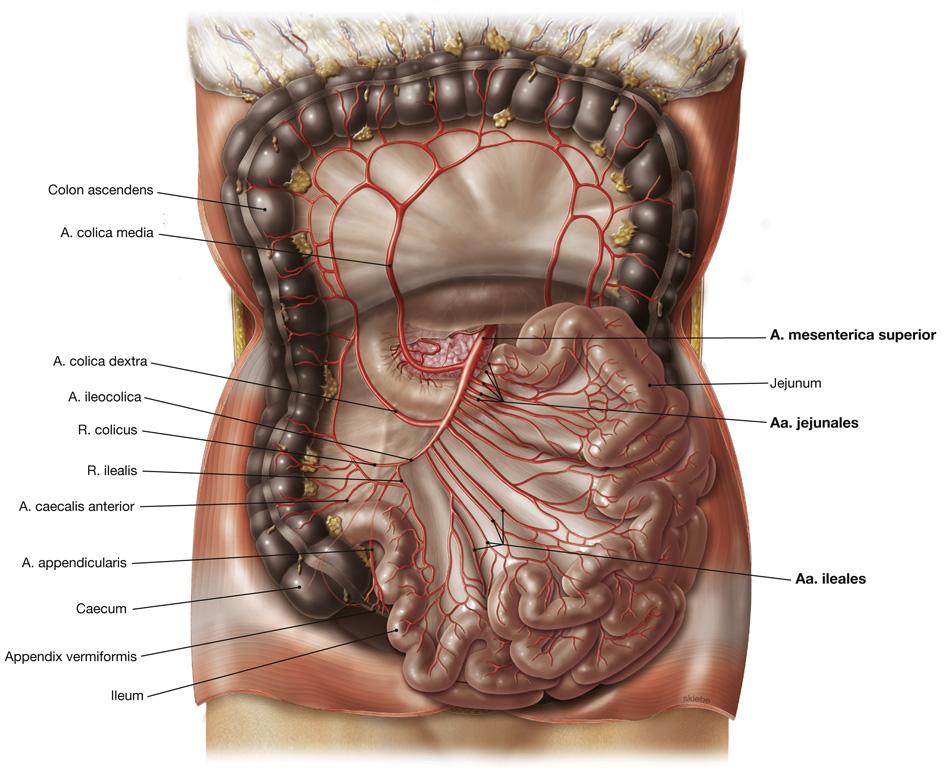

Fig 3.23: a. mesenterica superior (AMS)

|